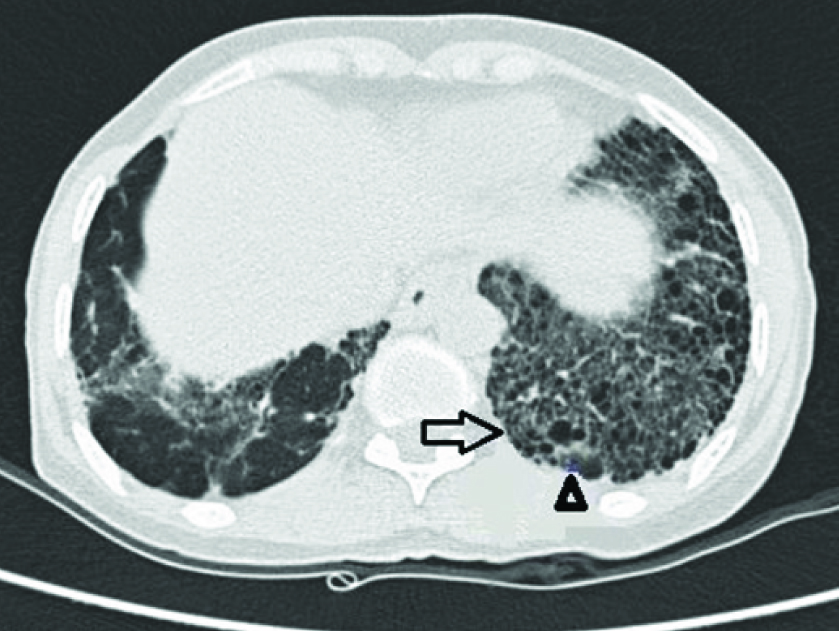

Haemogram showed normocytic normochromic anaemia (Hb=11.8 gm/dL), total leukocyte count of 12,100/mm3 with 71% neutrophils, 20% lymphocytes, and 1% eosinophils. Erythrocyte sedimentation rate was 61 mm in the first hour. Serum potassium level was 4.4 mmol/lit. Creatine kinase levels were low and showed a downward trend on serial monitoring. Anti-nuclear antibody and rheumatoid factor was negative. Serological testing for human immunodeficiency virus, sputum smear for acid fast bacilli was negative. Electrocardiogram, thyroid functions and liver functions were normal. Spirometry showed a restrictive pattern. Chest roentgenography revealed bilateral reticular opacities with honeycombing appearance, predominantly in the middle and lower zones. HRCT of the thorax was suggestive of Usual Interstitial Pneumonia (UIP) pattern [Table/Fig-1] and did not show any abnormality of the thymus gland. Magnetic Resonance Imaging (MRI) of the spine did not show any evidence of cord compression. Patient was followed up to check for progression of neurological symptoms. After one month, patient complained aggravation of weakness and nerve conduction study showed typical decrement of response in the right median nerve, left median nerve, facial nerve and accessory nerve to trapezius. Repetitive Nerve Stimulation (RNS) test was performed which yielded a decrement in compound muscle action potential amplitude of more than 10 percent, thus indicating a positive RNS test. Acetylcholine receptor (AchR) auto antibodies levels were normal. Based on the clinical features and a positive RNS test, the clinical diagnosis of myasthenia gravis was considered.

HRCT showing interstitial thickening (arrow) and honey combing (arrowhead) in the basal regions of the lung.

Idiopathic pulmonary fibrosis is a disease affecting lungs that is characterized by progressive lung fibrosis. It has an estimated incidence of 7 to 17 per 100000 person years with a prevalence of 20-60 per 100000 person years as per the western scenario [1]. Inspite of the recent rise in IPF in India, the incidence and prevalence of the disease in India is difficult to determine as there are very limited epidemiological studies available [2]. For definitive diagnosis of IPF, a surgical lung biopsy is needed, but in this patient, a diagnosis was made in view of the clinical features and typical HRCT findings of areas of interstitial thickening and honey combing in basal regions [3]. On the other hand, myasthenia gravis is a progressive autoimmune disorder in which antibodies are directed against the neuromuscular junction. The annual incidence of MG is 3-4 cases per million and has a prevalence of about 60 cases per million in the general population [4]. There are no widely accepted diagnostic criteria or guidelines for diagnosis of myasthenia gravis. Clinical features, serological testing and electrophysiological studies are used to support the diagnosis. About 10-20% of generalized myasthenia gravis can have negative AChR antibody, as was the case in our patient. In such cases, anti muscle-specific kinase serology testing is to be done. However this facility is not available in our set up. However, if serology is inconclusive, then electrophysiological testing i.e., RNS is done. RNS test has a specificity of 97% for myasthenia gravis [5]. Though it can sometimes be negative, RNS testing has a crucial role in diagnosing seronegative myasthenia gravis [6]. A positive RNS test and improvement of muscular weakness with pyridostigmine lead to the diagnosis of myasthenia gravis in this patient even though AChR antibodies were negative. A variety of neuromuscular conditions can cause bilateral upper and lower limb muscle weakness. In this case, a diagnosis of Lambert Eaton myasthenic syndrome was excluded as improvement of muscular condition was not seen with exercise. A diagnosis of steroid induced myopathy was ruled out as the patient’s condition worsened after stopping steroids. Since the patient had none of the characteristic skin lesions and in view of the normal values of creatine kinase enzyme on serial monitoring, polymyositis and dermatomyositis were ruled out. HIV and hypothyroidism as causes of muscular weakness were ruled out in view of negative serology. Inspite of normal AChR autoantibody levels, the clinical features and a positive RNS test pointed to myasthenia gravis and the improvement of the patient’s condition with pyridostigmine pointed to the current diagnosis.